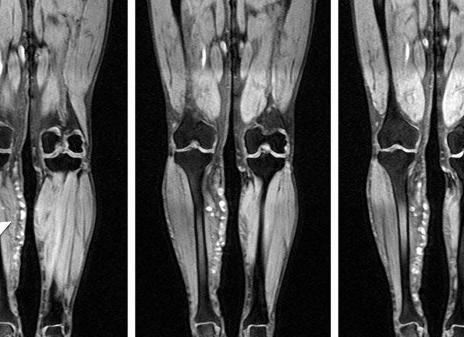

Что покажет МРТ голени

Патологии этой области наиболее трудно диагностируемые. По этой причине часто применяется контрастный препарат.

В ходе МРТ определяется состояние костной ткани голеностопного сустава, хрящей, связочного аппарата, соседствующих суставов.

Снимки, полученные после исследования, помогают определить патологии сухожилий и мышечной ткани, диагностировать воспалительный процесс в локальной зоне.

МРТ голени

МРТ голени является высокоэффективным методом исследования мягких тканей и сухожилий, суставов и костей, связок, сосудов и нервов голени. МРТ голени позволяет выявить широкий спектр заболеваний, в том числе доброкачественные и злокачественные новообразования на ранних стадиях.

Что позволяет выявить МРТ голени

МРТ голени позволяет определить:

- различные травмы мягких тканей голени;

- локализацию инородных тел;

- травмы и повреждения голеностопного и коленного суставов;

- воспалительные изменения тканей голени;

- посттравматические процессы;

- доброкачественные и злокачественные опухоли;

- метастазы в мягких тканях голени;

- состояние сосудов и нервов;

- степень выраженности воспалительного процесса;

- повреждения сухожилий и связок.

Голень является таким отделом ноги, который наиболее тяжело диагностировать. По этой причине пациентам, проходящим обследование, назначается контрастирование. На полученных после сканирования изображениях видно состояние мягких тканей голеностопа, нервов нижних конечностей, связок и хрящей. Благодаря этому можно определить повреждения сухожилий и мышц и заметить воспалительный процесс мягких тканей голени.